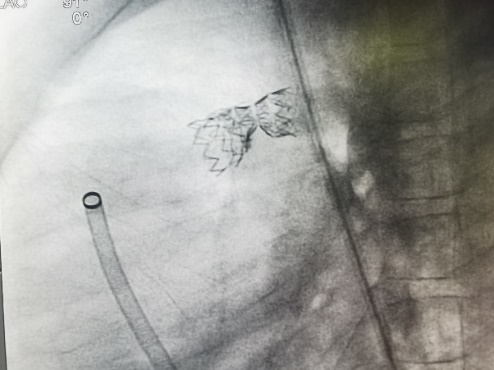

术前显示原植入支架断裂

在导丝引导下,右心导管通过断裂的支架,到达左肺动脉远端。再沿导丝送入Pul-Stent,和球囊载体,覆盖断裂的支架。